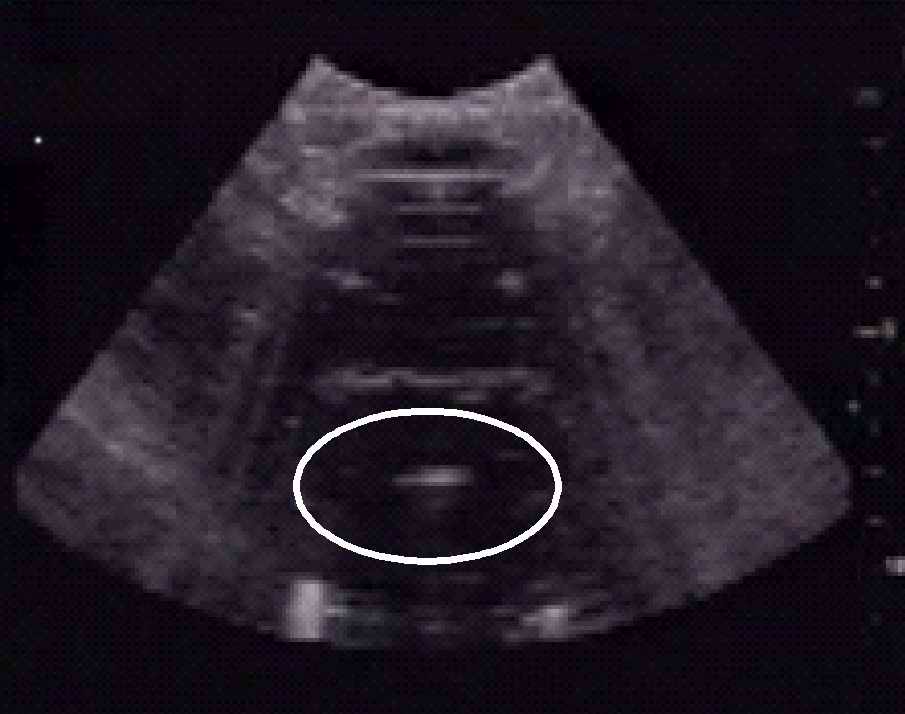

Рис. 3. Области теплового некроза, полученные в образце ткани печени при воздействии мощного фокусированного ультразвука. Рис. 4. Визуализация воздействия HIFU на ткань в режиме реального времени по регистрации рассеянного на возникающих пузырьках кипения диагностических импульсов УЗИ.

Хотя тепловой механизм является доминирующим в воздействии ультразвка на ткань, важный вклад часто вносят и другие физические механизмы, характерные для взаимодействия УЗ с тканью: кавитация (образование пузырьков и их колебания в поле волны), кипение (Рис.4), сдвиговые напряжения, течения. Эти механизмы, их вклад в разрушение ткани, возможность их использования для контроля за процедурой HIFU в режиме реального времени до конца не поняты и представляют собой интересный объект физических исследования, как в теории, так и экспериментально.